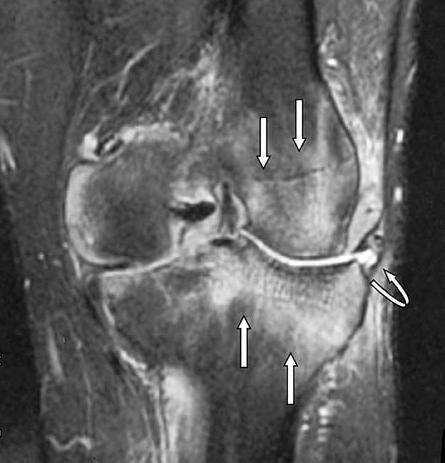

El edema óseo es una acumulación de líquido en el interior del hueso, generalmente en la médula ósea. Suele detectarse mediante resonancia magnética y está asociado a procesos inflamatorios o sobrecargas.

En la rodilla, puede afectar a estructuras como el fémur, la tibia o la rótula.